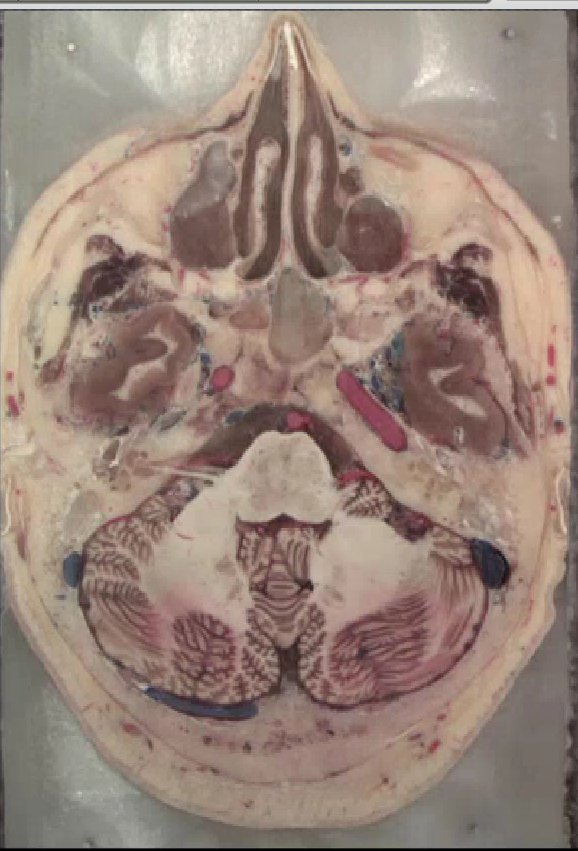

Caudal Pons

Rostral Medulla

Caudal medulla

Middle Pons

Rostral Pons

Caudal Midbrain

Rostral Midbrain